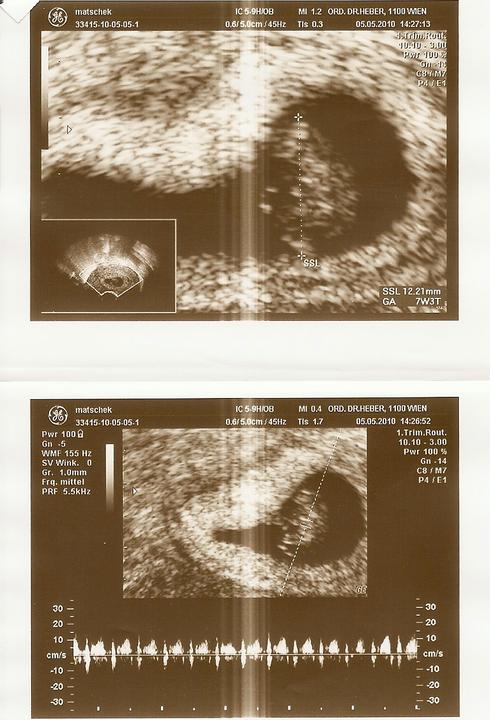

Hmm dnes sa ide do nemocnice na vysetrenie NT

Videla som mojho cervika!!!nadherne si tam robil party